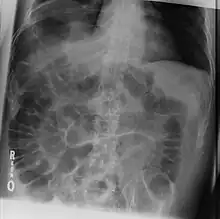

The dark areas on both sides of the intestines indicate that air is present in both sides. This is called "Rigler's sign".